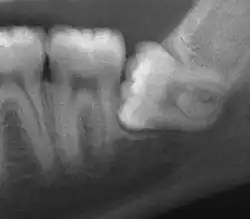

| Impacted wisdom tooth with a horizontal orientation | |

An ectopic tooth, also known as an impacted tooth, is a tooth that develops in an abnormal position (ectopia) and fails to erupt into its normal location in the oral cavity.[1] [2] Ectopic teeth can cause a variety of symptoms, such as pain, swelling, and infection, and they can lead to more serious complications if left untreated.

Diagnosis of ectopic teeth typically involves a comprehensive dental examination, including X-rays and other imaging tests. Treatment options for ectopic teeth depend on the location and severity of the condition, as well as the age and overall health of the patient. In some cases, observation and monitoring may be sufficient, while in other cases, surgical intervention may be necessary to remove the ectopic tooth and prevent further complications.[5]